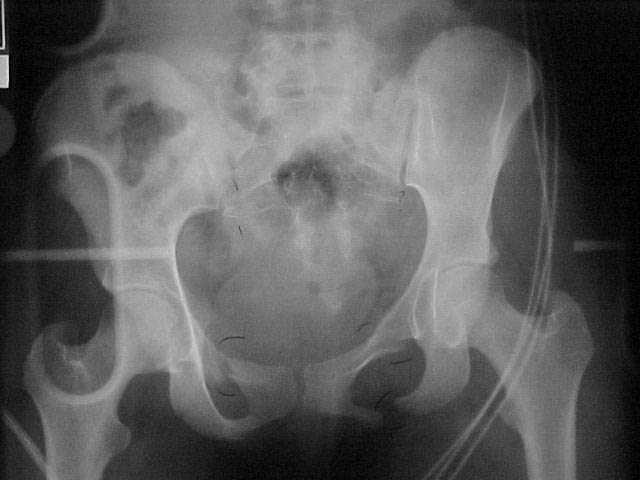

A 17 year old female involved in a car crash. Has a Type III lateral compression injury to her pelvic ring using the Young-Burgess classification. A windswept pelvis if you will. The images are included. There appears to be posterior displacement of the left hemipelvis as well.

Fx/Injury Evaluation:

Impression: unstable, requires reduction with stabilization, will continue with continued deformity if not stabilized

Thanks for submitting your case to the forum, I am sure you will soon be toxic with recommendations that you will have to filter through. I would like to offer some rather elementary advice: Your patient needs to have appropriate inlet and outlet films adjusted for her anatomy;i.e.,she appears to be somewhat lordotic and that would require the gantry angle to be adjusted with each view. The same would be true for the CT scan it appears as though the angle of the gantry is tangential to the slope of the sacrum (sacro-horizontal line if you will) and that gives a distorted view of the posterior ring injury.